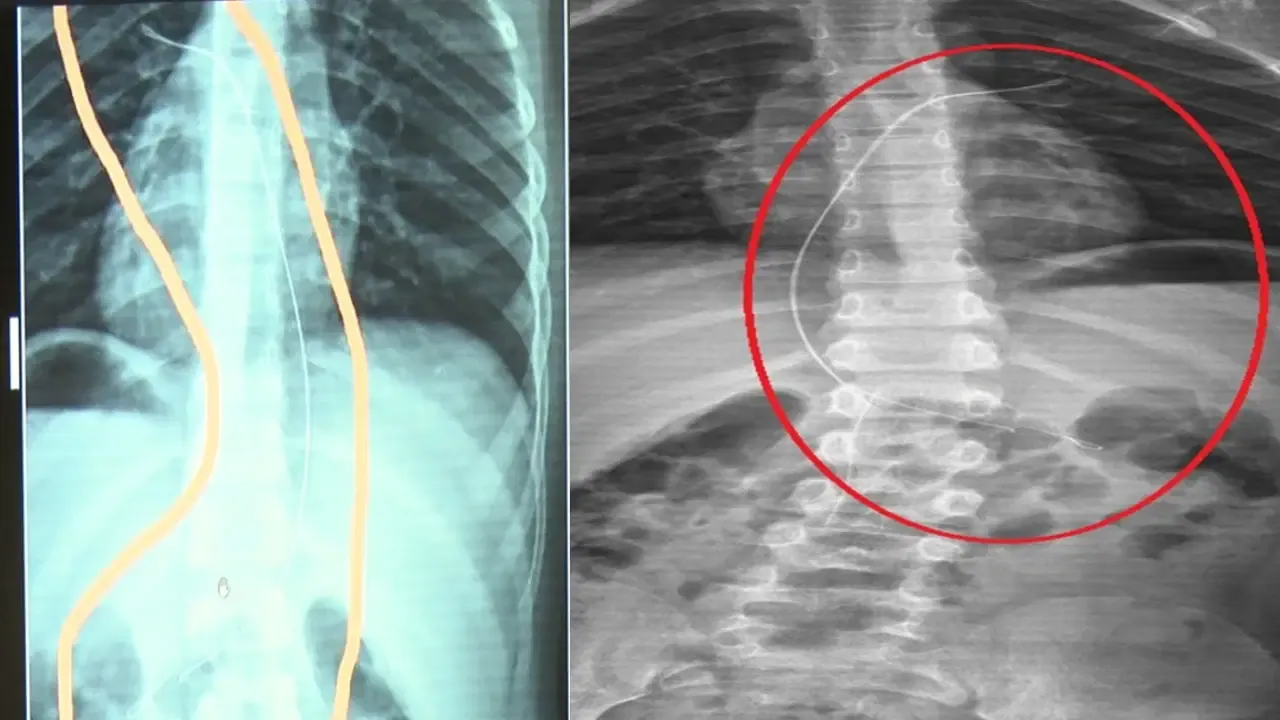

Şırnak’ta yaşayan Semra (37) ve Mehmet Ötün (40) çiftinin oğulları Aram Devran Ötün, mayıs ayında piknikteyken salatalık parçası yuttuktan sonra öksürük ve kusma şikâyetleri görülünce Şırnak Devlet Hastanesi’ne götürüldü. Burada çekilen röntgen ve MR’da Aram’ın vücudunda kateter unutulduğu görüldü.

Diyarbakır’daki Gazi Yaşargil Eğitim ve Araştırma Hastanesi Kadın Doğum ve Çocuk Ek Binası’na sevk edilen Aram, 5,5 saat süren riskli bir ameliyata alınarak 18 santimetre uzunluğundaki kateter çıkarıldı.

Ameliyat sonrası yapılan incelemelerde kateterin kalp kapakçığına ve ciğerlerine zarar verdiği belirlendi.

Ailenin avukatı Ahmet Yalçın, hastane hakkında hem şikâyetçi olduklarını hem de dava açtıklarını belirterek, “Müvekkilim Aram Devran Ötün, 2022 Eylül ayında Dicle Üniversitesi Hastanesi’nde Stevens- Johnson hastalığı nedeniyle tedavi gördü. Tedavi sırasında kendisine kateter takıldı. 18 santimetre uzunluğundadır. Bunu takarken büyük bir ihmalkarlık yapılarak vücudunda unutuldu. Mayıs ayında müvekkilim çok öksürdüğü için Şırnak Devlet Hastanesi’ne kaldırıldı. Burada yapılan tetkiklerde kateterin unutulduğu tespit edildi. Daha sonra Diyarbakır Gazi Yaşargil Kadın ve Çocuk Hastalıkları Hastanesi’ne götürüldü. Çok riskli bir ameliyata alındı ve kateter çıkarıldı. Bu kateterin vücutta yol aldığı tespit edildi. İlk giriş yeri ve çıkarıldığı yer arasında çok fark var ve kalp kapakçığı ile ciğerlerine zarar verdiği tespit edildi. Müvekkillerimin hem maddi hem de manevi zararlarını karşılamak adına Dicle Üniversitesi’ne biz başvuruda bulunduk. 30 günlük cevap süresi içerisinde bize geri dönüş yapılmadı. Biz de maddi ve manevi zararların tazminat için Diyarbakır İdare Mahkemesi’ne davamızı açtık ve sorumlulardan şikâyetçi olduk” dedi.